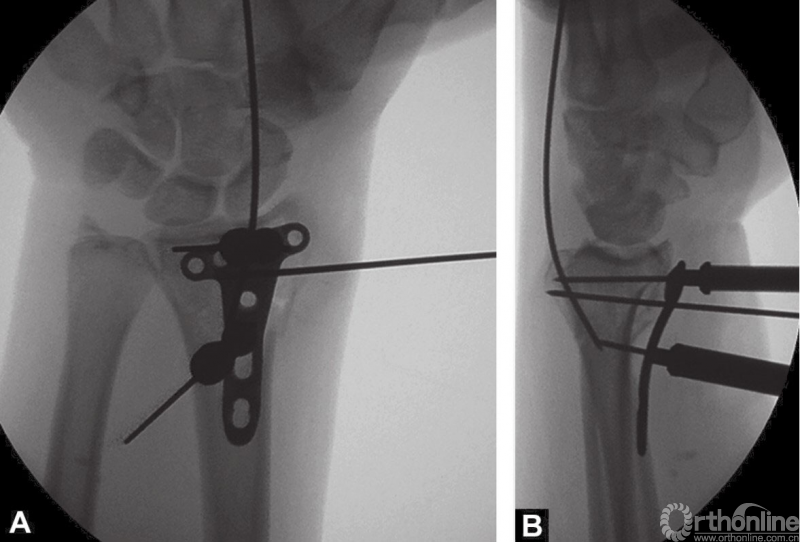

2.4mm桡骨远端T形锁定钢板安放锁定套筒后,置入桡骨远端掌侧面,克氏针通过套筒将钢板临时固定在桡骨远端(图4A和B)。

图4 A和B桡骨远端放置2.4mm锁定钢板和用克氏针临时固定

在软骨下置入远端锁定螺钉能够获得更好的稳定性。X线透视检查钢板放置情况。

远端的锁定螺钉首先置入。接着用一枚普通的2.4mm皮质螺钉置入,将钢板贴向桡骨远端骨面。

由于有远端固定角度的锁定螺钉,钢板紧贴桡骨干能够增加桡骨远端关节面的倾斜度,所以要选用最靠近桡骨干的螺钉孔置入头侧锁定螺钉(图5)。